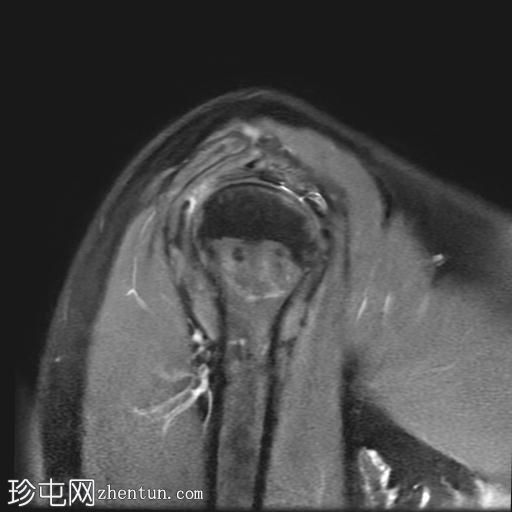

MRI

冠状位

T2加权像

T1加权像

冠状位PD加权像

脂肪抑制像

矢状位

PD加权像

肩袖钙化性肌腱炎:冈下肌腱上部纤维可见约7 x 14 mm的低信号病灶

冈上肌腱滑囊侧纤维可见轻度增高液体信号,提示肌腱病

肩峰II型

肩峰下滑囊可见轻度液体信号